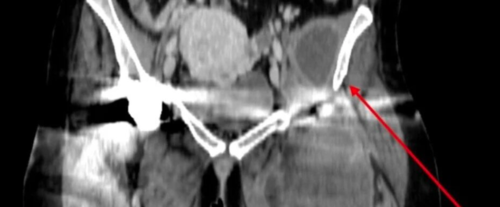

肩关节脱位占所有主要关节脱位的 50% 。前脱位最为常见,占病例的 95% 至 97%。后脱位占2%至4%,下脱位占0.5%。

前脱位的复位技术通常使用轴向牵引和/或外旋。不存在单一的完美或首选技术。最重要的是,操作者应熟悉多种技术,并使用适合患者脱位和临床状态的技术